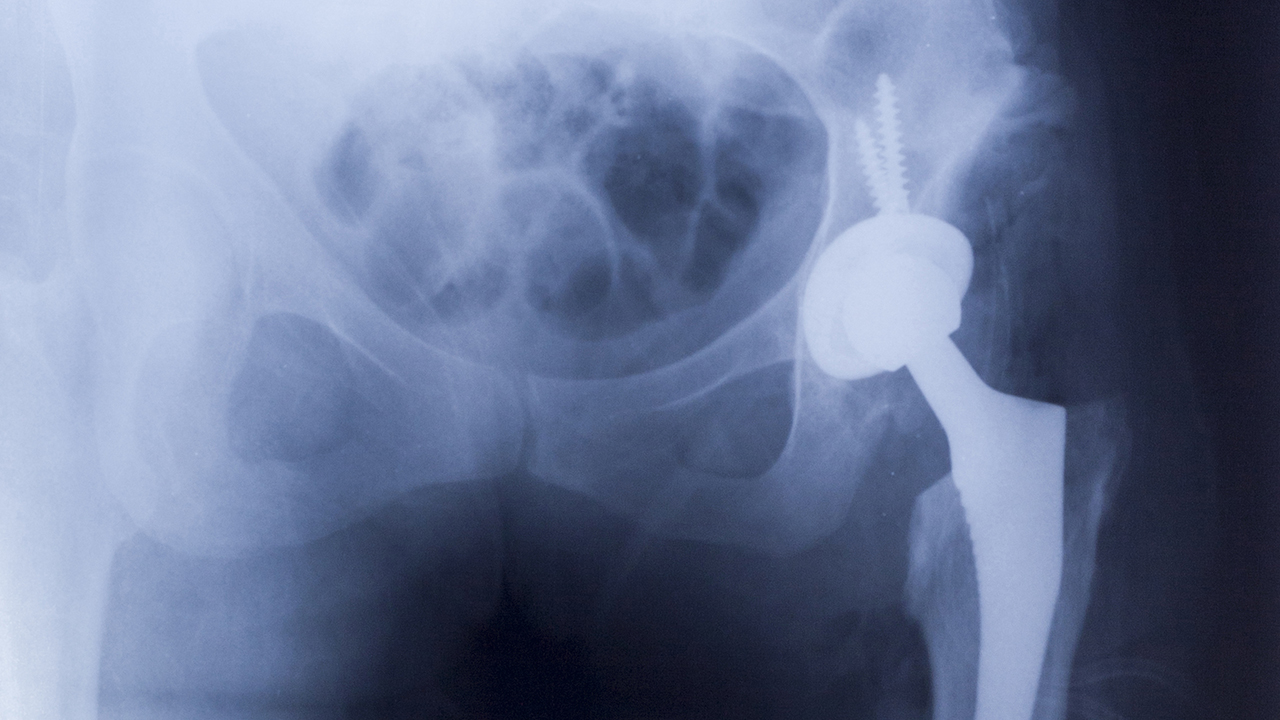

Er wordt een onderdeel van heupprothesen met metalen scharnierende vlakken van de markt gehaald. Voor de zoveelste keer, nadat er eerder al problemen waren met verschillende heupprothesen maar ook met heel wat andere soorten van implantaten. Hoeveel patiëntenleed is er nog nodig om de overheden te overtuigen strengere regels te maken?

Ditmaal is het de fabrikant Smith & Nephew die één van haar onderdelen van heupprothesen met metalen scharnierende vlakken van de markt haalt. Het gaat om de zogenaamde R3 metalen voering van hun kunstheupen. Uit gegevens van het heupregister van het Verenigd Koninkrijk blijkt dat dit onderdeel slechte resultaten geeft. Van de patiënten met dit implantaat heeft 6,3% een heringreep aan de heup moeten ondergaan nog geen 4 jaar na de plaatsing ervan. Volgens de normen van de overheid mag dit maximaal 4% zijn. De Britse overheid vraagt de chirurgen het onderdeel niet meer te gebruiken en de patiënten van nabij op te volgen opdat problemen snel ontdekt en aangepakt zouden worden.